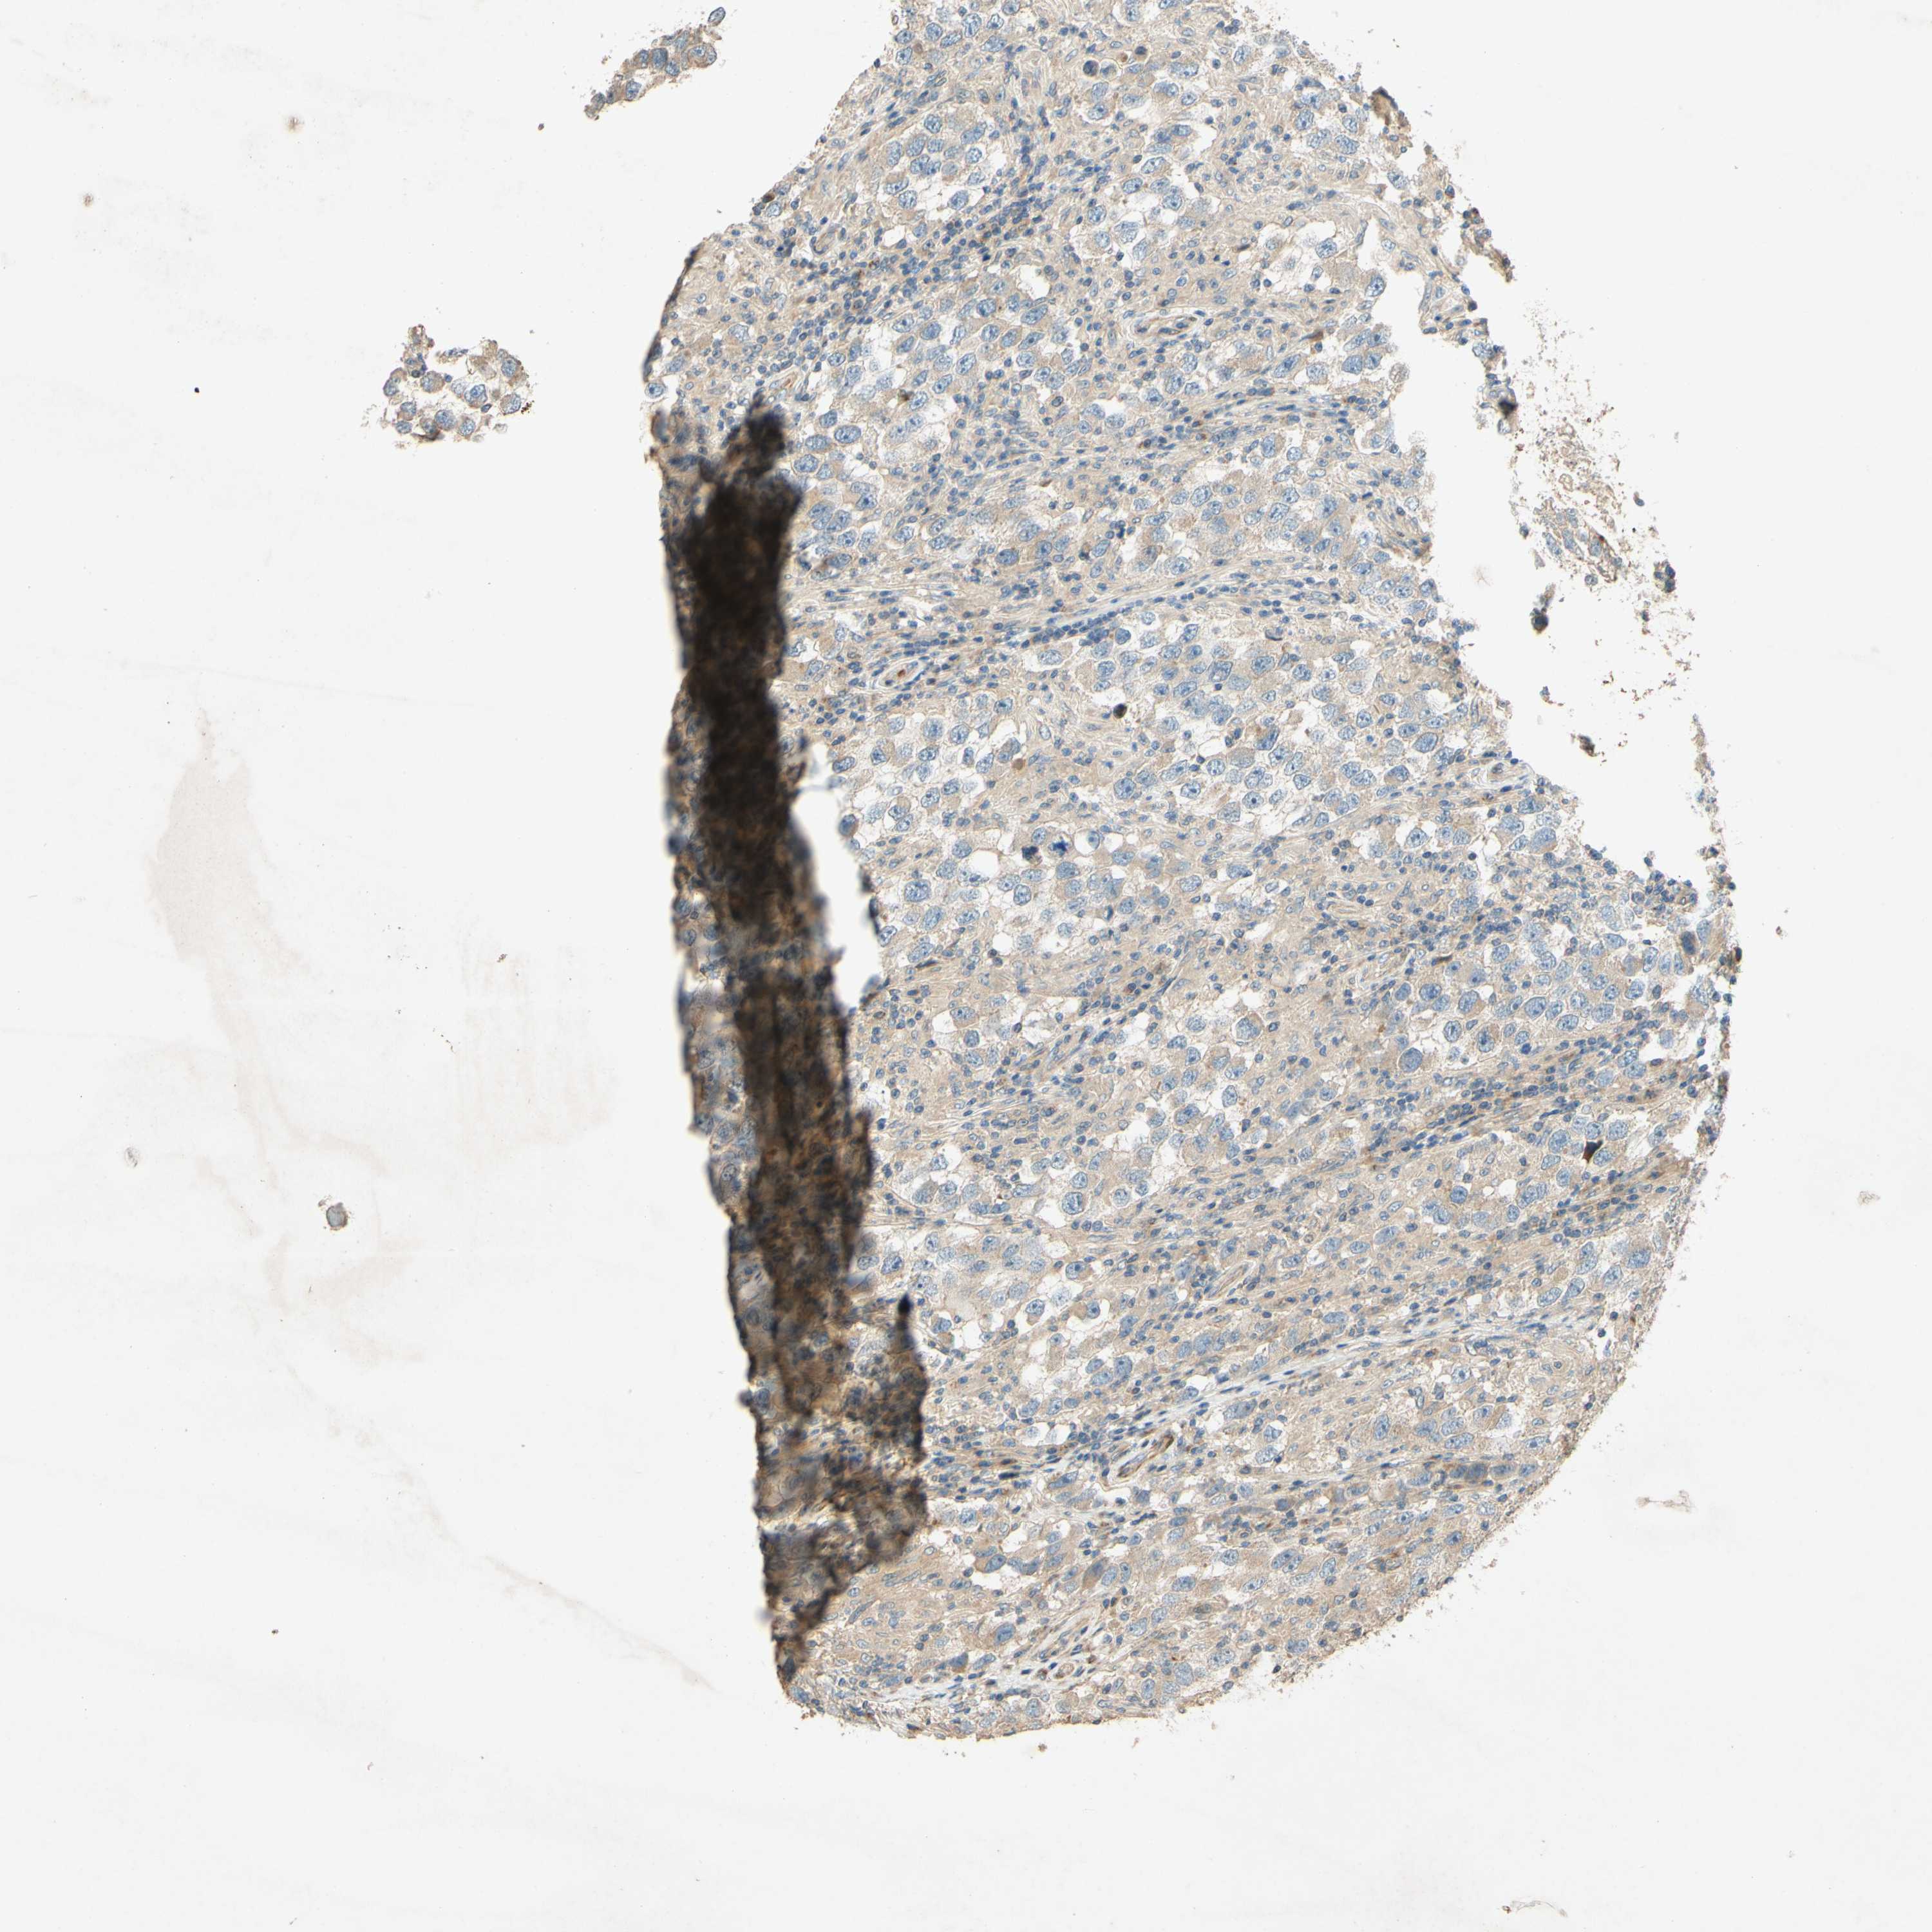

TESTIS CANCER - Protein expressioni

A mouse-over function shows sample information and annotation data. Click on an image to view it in a full screen mode. Samples can be filtered based on level of antibody staining by selecting one or several of the following categories: high, medium, low and not detected. The assay and annotation is described here.

Note that samples used for immunohistochemistry by the Human Protein Atlas do not correspond to samples in the TCGA dataset.

Antibody stainingi

Antibody staining in the annotated cell types in the current human tissue is reported as not detected, low, medium, or high, based on conventional immunohistochemistry profiling in selected tissues. This score is based on the combination of the staining intensity and fraction of stained cells.

Each image is clickable and will lead to virtual microscopy that enables deeper exploration of all samples and also displays staining intensity scores, fraction scores and subcellular localization as well as patient and tissue information for each sample.

Antibody HPA010738

Staining

High

Medium

Low

Not detected

Intensity

Strong

Moderate

Weak

Negative

Quantity

>75%

75%-25%

<25%

None

Location

Nuclear

Cytoplasmic/membranous

Cytoplasmic/membranous,nuclear

Carcinoma, Embryonal, NOS

Seminoma, NOS